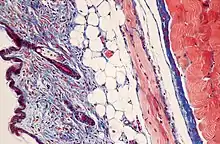

Masson's trichrome stain

Masson's trichrome is a three-colour staining procedure used in histology. The recipes evolved from Claude L. Pierre Masson's (1880–1959) original formulation have different specific applications, but all are suited for distinguishing cells from surrounding connective tissue.

Most recipes produce red keratin and muscle fibers, blue or green collagen and bone, light red or pink cytoplasm, and dark brown to black cell nuclei.

Standard applications: Masson's trichrome staining is widely used to study muscular pathologies (muscular dystrophy), cardiac pathologies (infarct), hepatic pathologies (cirrhosis) or kidney pathologies (glomerular fibrosis). It can also be used to detect and analyze tumors on hepatic and kidney biopsies.[1]